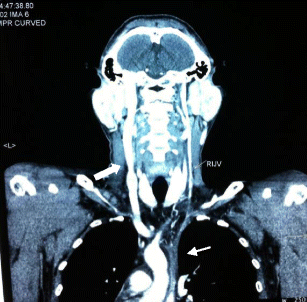

Fig. 1